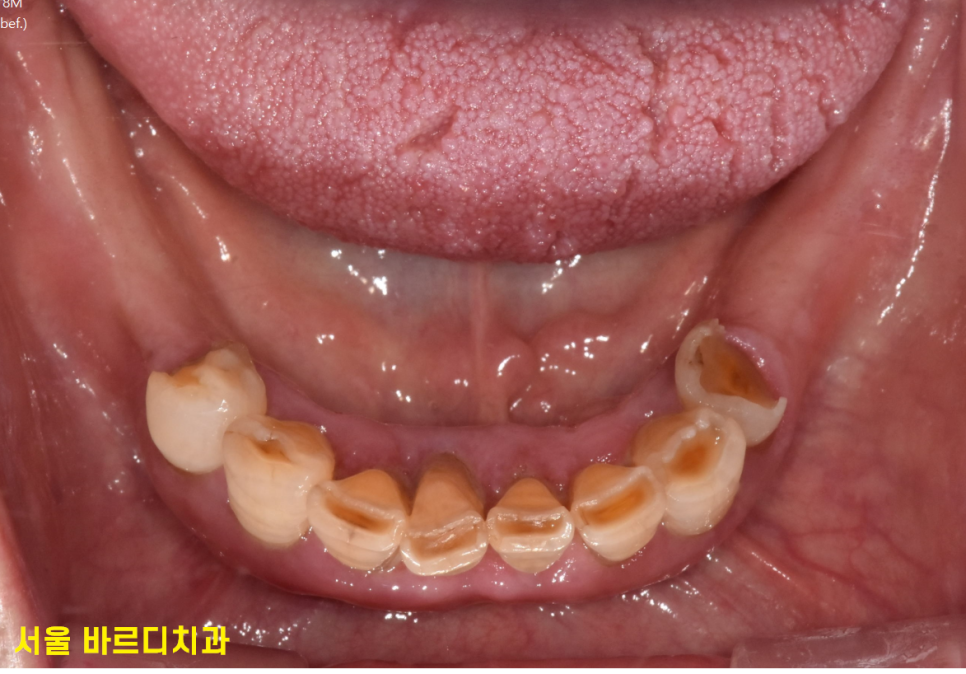

실제 구강은 이런 모습입니다.

전체적인 치아 치료 수준은 어느정도이냐!

상태들이 안좋아 이를 거의 다 뽑아야하는 정도입니다.

전악 치료라는 거죠~

오늘 환자분처럼 치아 곳곳에 충치가 심해 구멍이 뚫리고

뿌리만 남고 이미 상실된 치아도 많은 경우죠~